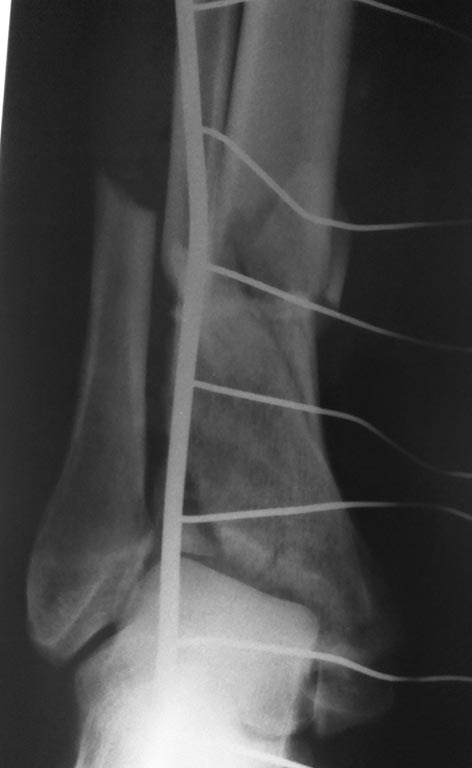

Снимки при поступлении, спустя 2,5 месяца. Рентген снимки после снятия

аппарата в архиве пришлю позже. Осылаю КТ от апреля.

Имя     : 2,5month lat.jpg